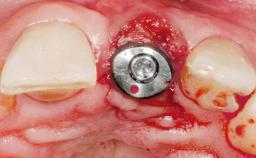

Immediate Flapless Placement of an Implant in a Maxillary Right Lateral Incisor Site

This 43-year-old male patient, a non-smoker, came to our practice because of a fracture of tooth 12 caused by a bicycle accident. Due to the combined para- and infrabony crown and root fracture, tooth extraction, and subsequent implant placement were suggested to the patient as the therapy of choice. The patient had high esthetic expectations with regard to the treatment outcome and asked for an immediate fixed provisional restoration. His individual esthetic risk profile summed up to a medium esthetic risk.

# of Implants 1

Type of Implants Two-Piece

Placement Protocol Immediate implant placement

Tooth Site Maxillary incisor or canine

Loading Protocol Immediate

Retention Screw-retained Screw-retained